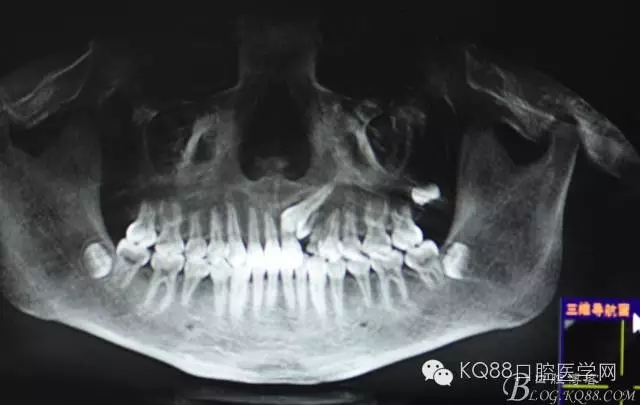

圖1.術(shù)前的cbct影像檢查:23位于腭側(cè)、牙齒位置比較高。

圖2.全景片影像檢查:23牙冠的遠(yuǎn)中還有一顆22畸形牙、及63滯留